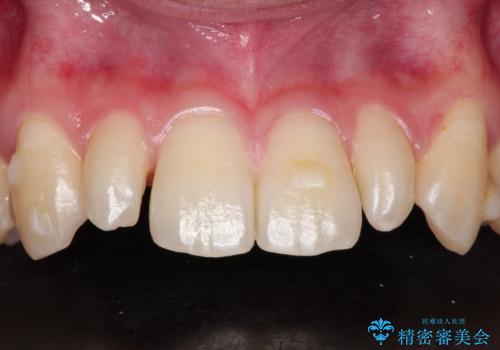

- 当院で矯正治療を行っており、上の前から2番目の歯の形も気になるので治したいと希望がありました。

矮小歯といわれる通常よりも小さい歯であったので、こちらにオールセラミッククラウンを装着して自然な歯の形にすることにしました。